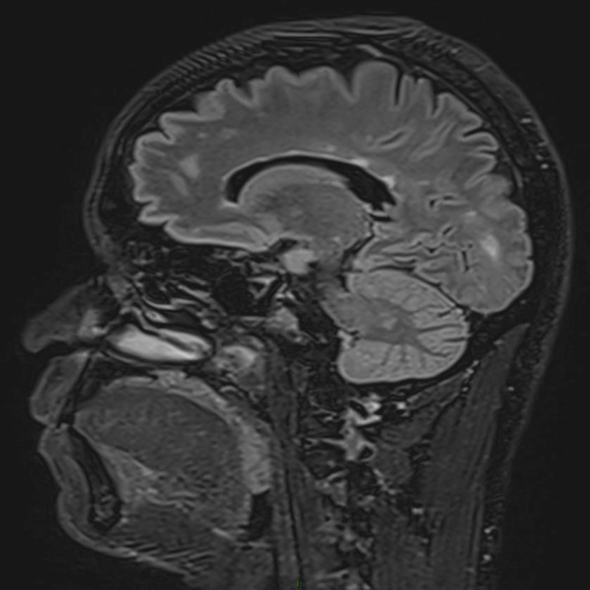

Le patient rapporte depuis trois semaines une diplopie lorsque ses deux yeux sont ouverts, qui disparaît à l’occlusion d’un œil. Il rapporte aussi une sensation d’instabilité à la marche avec une faiblesse de l’hémicorps gauche qui s’aggrave progressivement. Il ne décrit pas de sensation de rotation de lui-même ou de la pièce. Il a vu un ORL qui a prescrit un traitement symptomatique des vertiges, sans efficacité, raison pour laquelle il vous consulte.